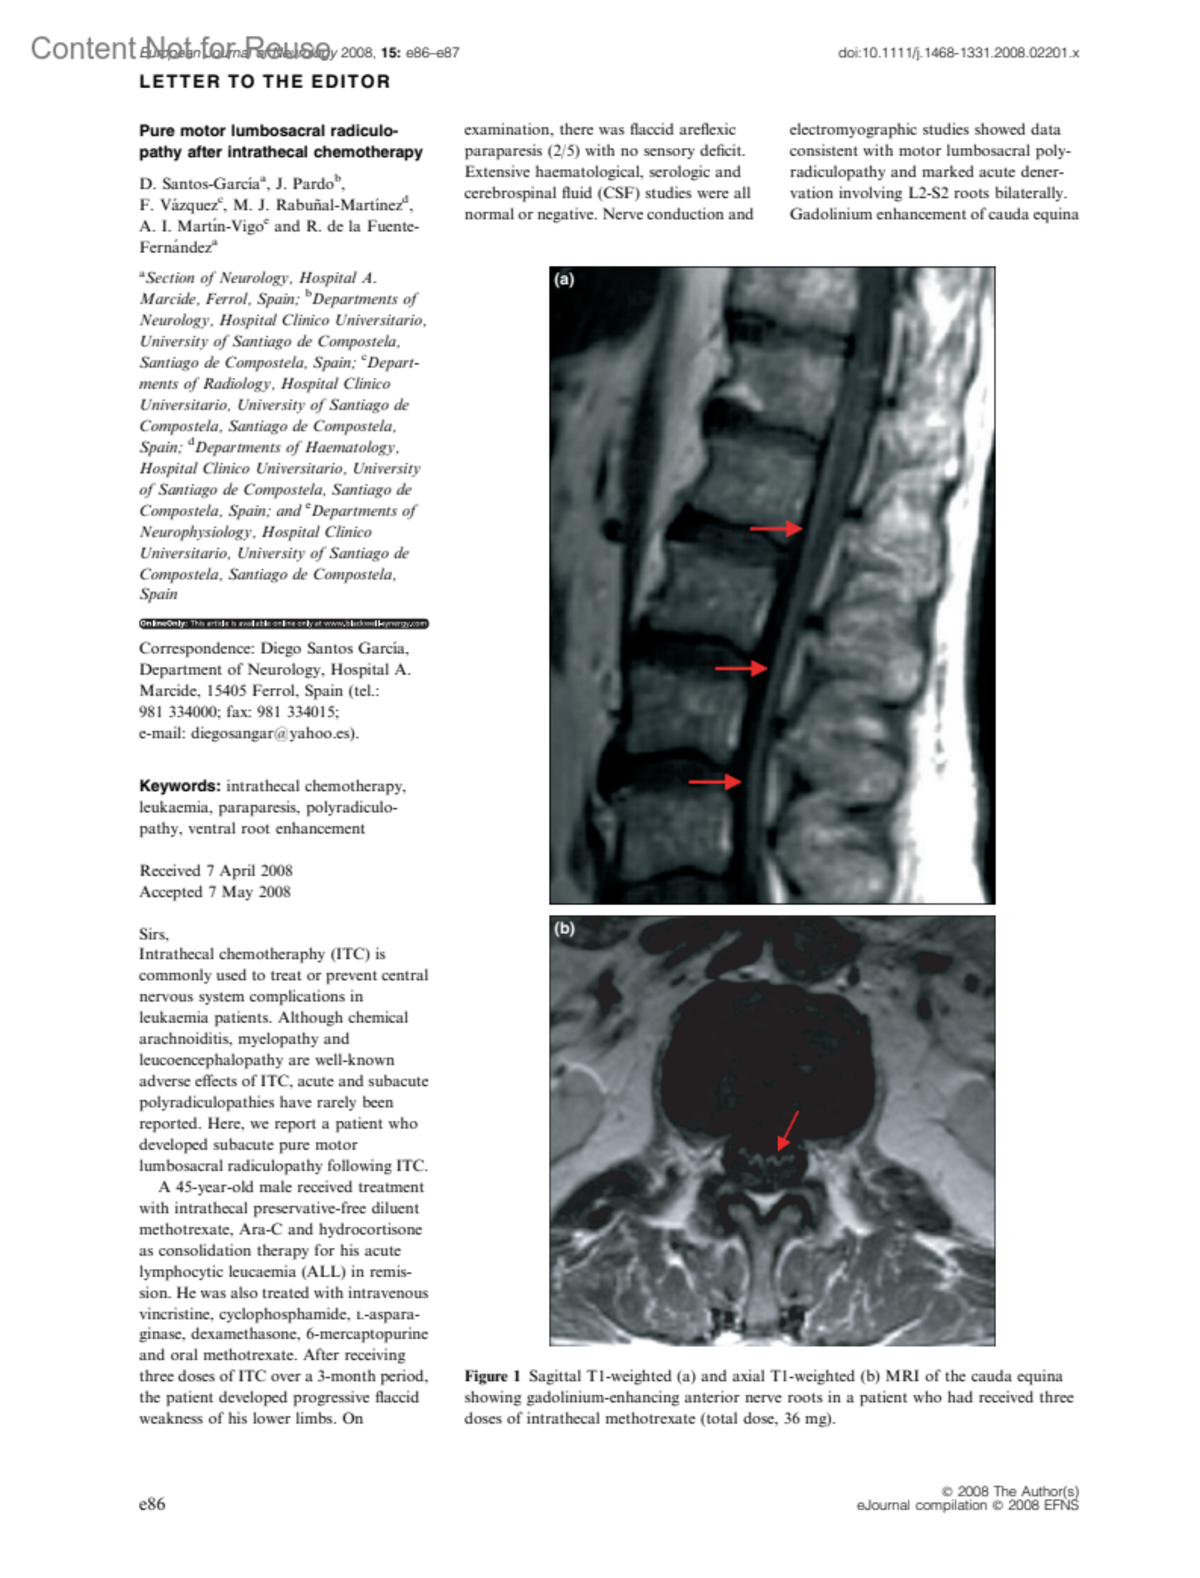

Received 7 April 2008; Accepted 7 May 2008